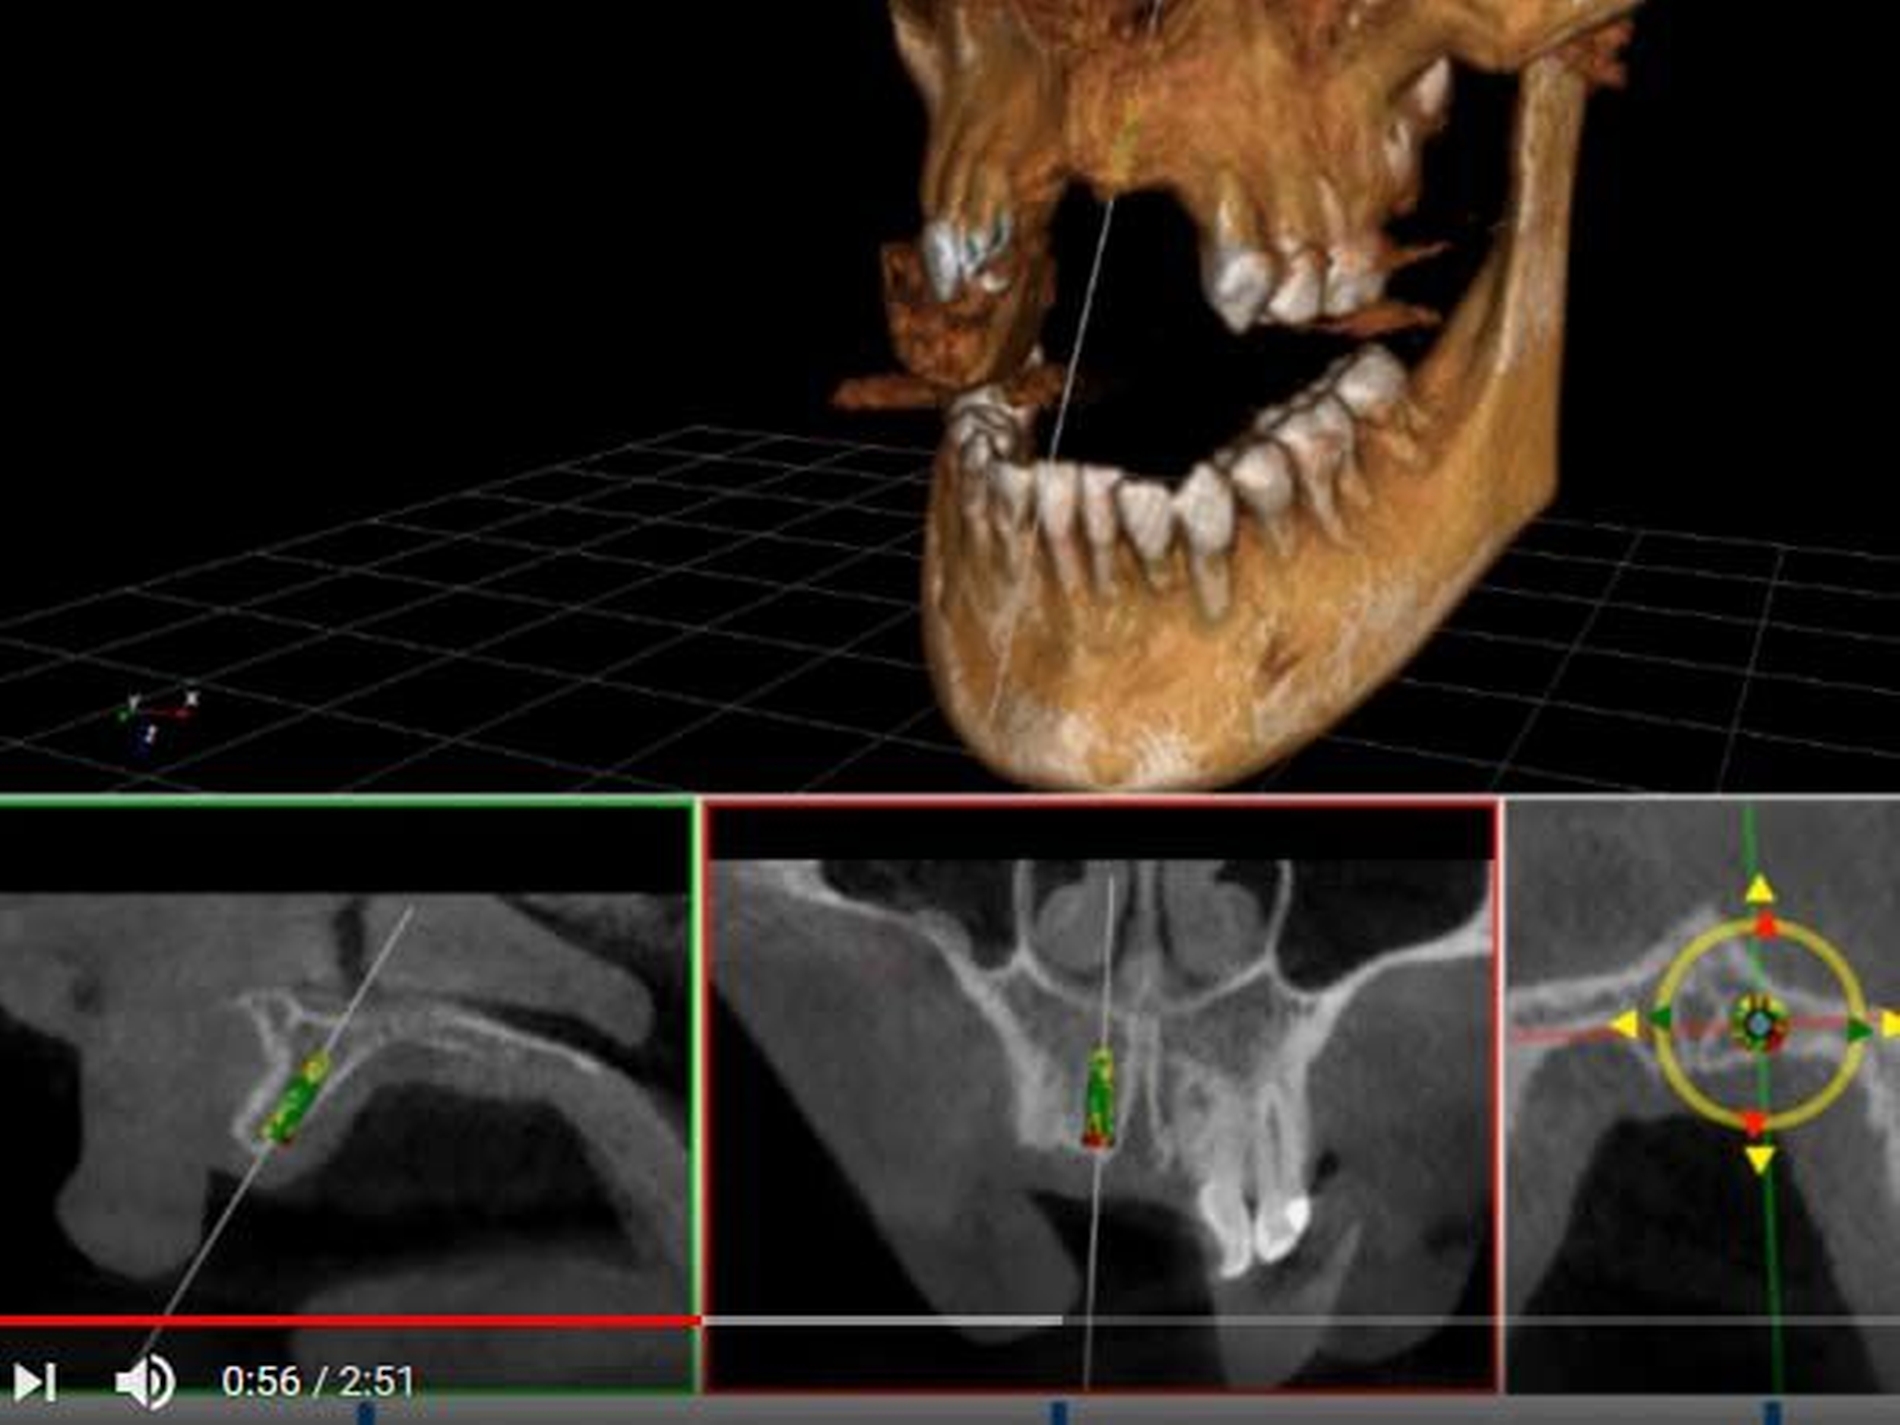

Die Idee des Herstellers: Auf Grundlage einer Computertomografie plant der Operateur in der Software die ideale Position, Ausrichtung und Tiefe des Implantats. Anschließend überprüft der Roboterarm, ob der Bohrer richtig platziert und geführt wird. Gleichzeitig soll die Software erlauben, das Operationsgeschehen als digitales Mischbild von CT und projizierter Bohrerposition auf einem Monitor zu verfolgen.

Das folgende Herstellervideo zeigt ein klinisches Anwendungsbeispiel: